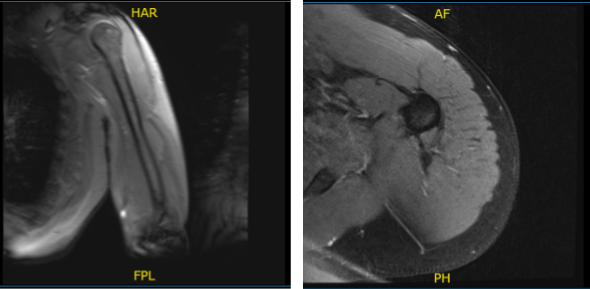

MRI results were presented and reviewed by the doctor. It showed that there is traction cyst in the greater tuberosity. There is a complete tear of the distal biceps’ tendon with tendon retraction to the level of the radial capitellum joint line with fluid along the course.

MRI-3T Left Arm Non-contrast